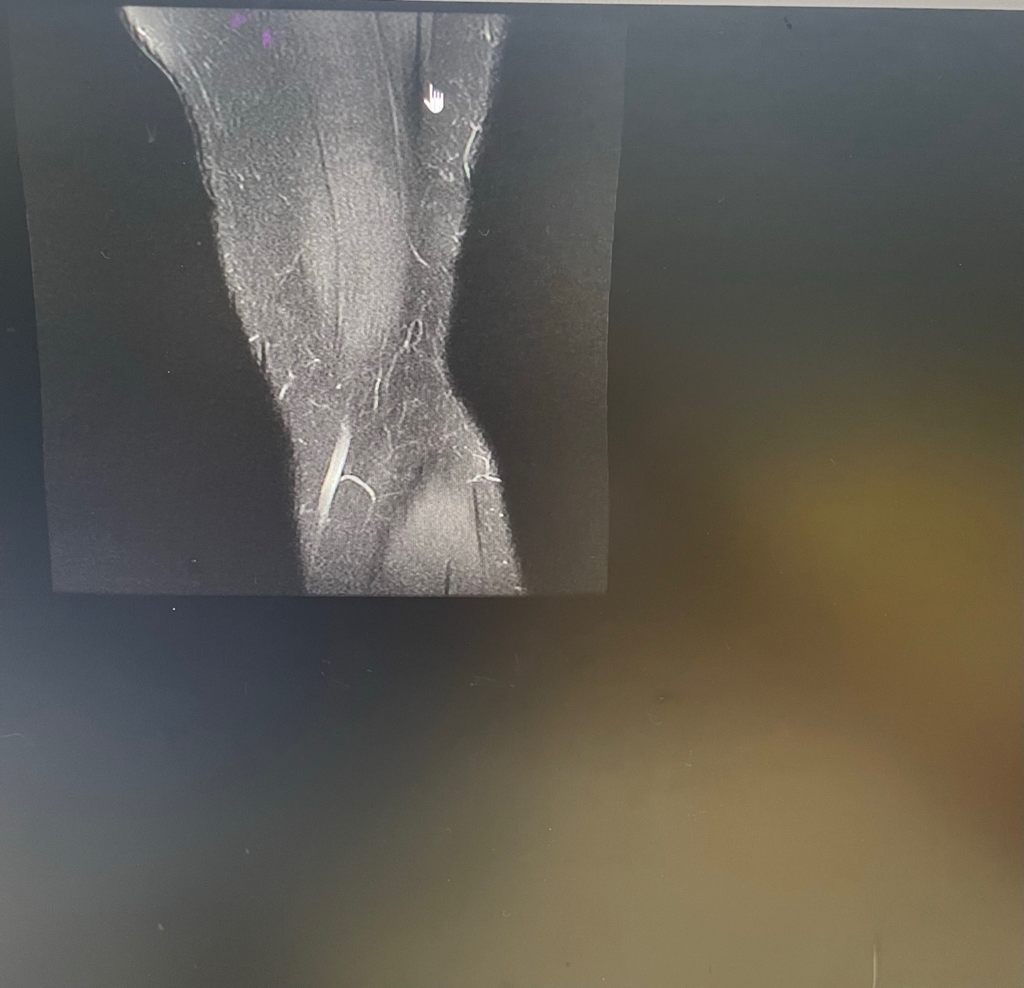

무릎이 너무 자주 아파서 mri를 찍어봤는데 무릎 연골에 이상이 있을까요

무릎이 선천적으로 원형연골인지 봐주시면 감사하겠습니다

• 1번 째 사진

MRI 판독에는 퇴행성 연골 손상, 바깥쪽 원판형 반월상 연골 이 의심된다고 적혀 있습니다.